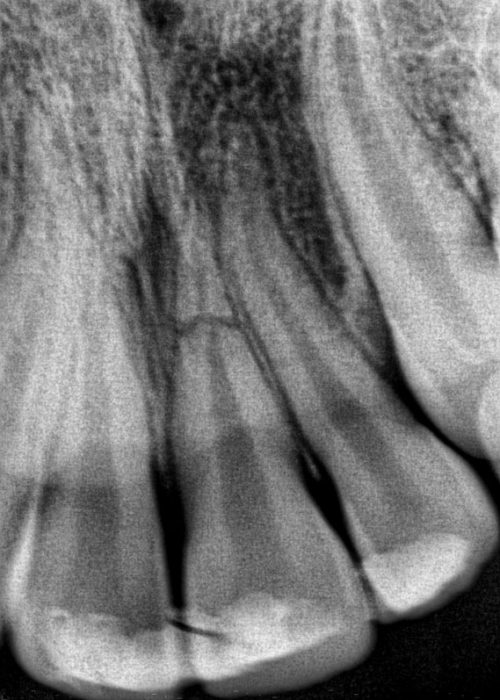

Injuries to the mouth can cause teeth to be pushed back into their sockets. Your endodontist or general dentist may reposition and stabilize your tooth. Root canal treatment is usually started within a few weeks of the injury and a medication, such as calcium hydroxide, will be placed inside the tooth. Eventually, a permanent root canal filling will be placed.

Sometimes a tooth may be pushed partially out of the socket. Again, your endodontist or general dentist may reposition and stabilize your tooth. If the pulp remains healthy, then no other treatment is necessary. Yet, if the pulp becomes damaged or infected, root canal treatment will be required.